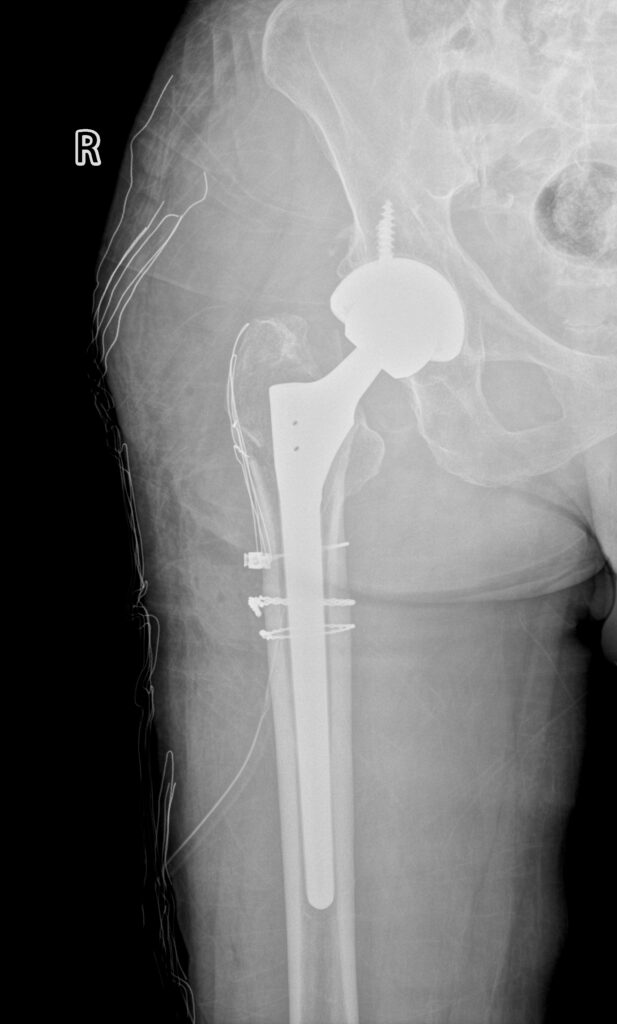

全髋术后股骨侧假体周围骨折切开复位内固定股骨柄翻修术(Open reduction, internal fixation and femoral stem revision for periprosthetic fractures on the femoral side after total hip surgery)